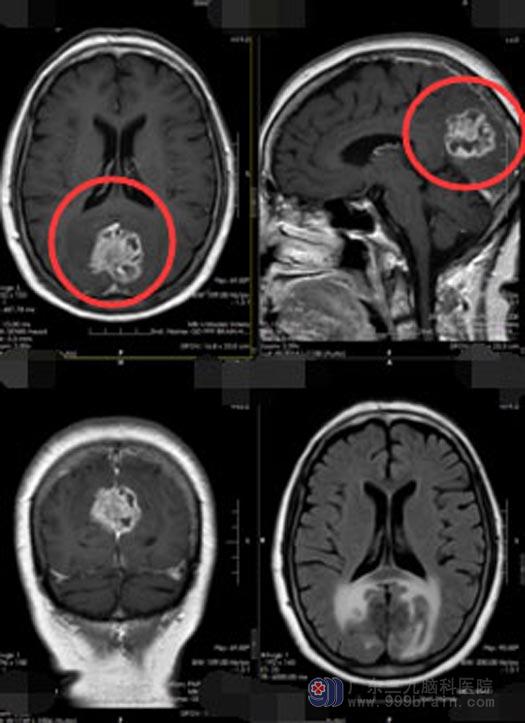

入院后,李阿姨的女儿始终抱着积极的心态,主动和主管医生进行沟通:妈妈身体一向很好,心态也乐观,我们决定争取一下。进一步头颅MR检查提示:1、大脑镰后部占位性病变,脑膜瘤可能,2、脑白质少许变性灶,3、幕上轻度脑皮质萎缩,4、部分空泡蝶鞍,5、右侧筛窦少许炎症、左侧上颌窦粘膜下囊肿;头颅+颈部CTA检查示:双侧顶枕部跨大脑镰占位性病变内存在多发小血管,考虑为脑膜瘤,病变包绕直窦,后缘紧贴上矢状窦。

控制好李阿姨的血压和血糖后,鲁明主任带领神经外五科的手术团队在全麻下为李阿姨行“双侧枕叶大脑镰窦旁脑膜瘤切除+矢状窦修补术”,术中可见肿瘤质韧,血运丰富,与脑组织边界不清,有部分粘连,肿瘤内邻矢状窦、大脑镰,基底位于大脑镰向两侧生长,侵及上矢状窦颌下矢状窦;分块切除肿瘤,肿瘤大小约5.5cm×5.0cm×5.0cm。